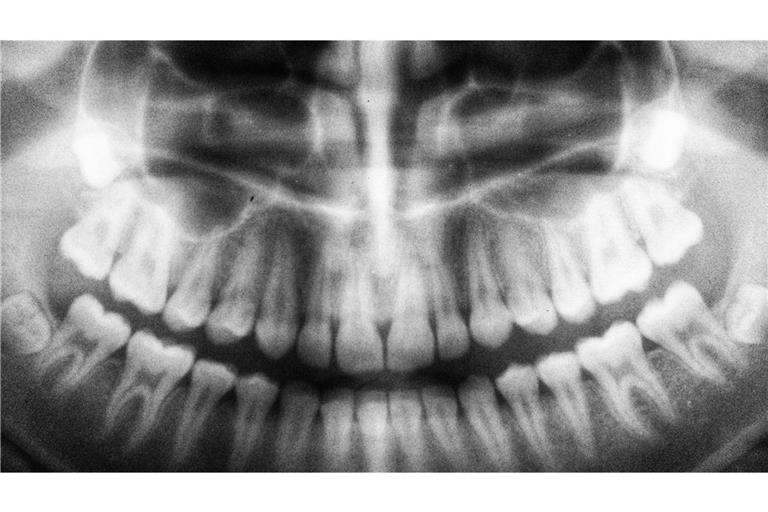

Weisheitszähne sind ein Überbleibsel der Evolution – und bereiten oft Probleme. Doch wann ist eine Operation wirklich nötig? Und welche Risiken bestehen?mehr...